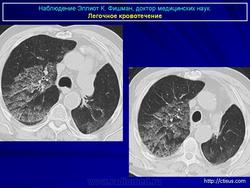

Лёгочное кровотечение. Fri, 23/09/2011 - 23:36 #1 Катенёв Валенти... Offline Last seen: 7 years 5 months ago Joined: 22.03.2008 - 22:15 Posts: 54876 Продолжение.Приложения: Sat, 02/06/2012 - 01:19 #2 Катенёв Валенти... Offline Last seen: 7 years 5 months ago Joined: 22.03.2008 - 22:15 Posts: 54876 Лёгочная геморрагия.Приложения: Sun, 03/06/2012 - 21:48 #3 Nikolas Offline Last seen: 1 month 4 weeks ago Joined: 21.12.2010 - 20:37 Posts: 4560 уважаемый Валентин Львович, что Вы почти всегда даете литературную справку во время какой-либо дискуссии. Ваши иллюстрации на мое клиническое наблюдение, как всегда, своевременны и актуальны. Спасибо. С уважением Nik. Sun, 03/06/2012 - 21:41 #4 Катенёв Валенти... Offline Last seen: 7 years 5 months ago Joined: 22.03.2008 - 22:15 Posts: 54876 Я постараюсь в ближайшее время пополнить этот набор. Wed, 10/09/2014 - 13:20 #5 Катенёв Валенти... Offline Last seen: 7 years 5 months ago Joined: 22.03.2008 - 22:15 Posts: 54876 Продолжение.Приложения:

Продолжение.